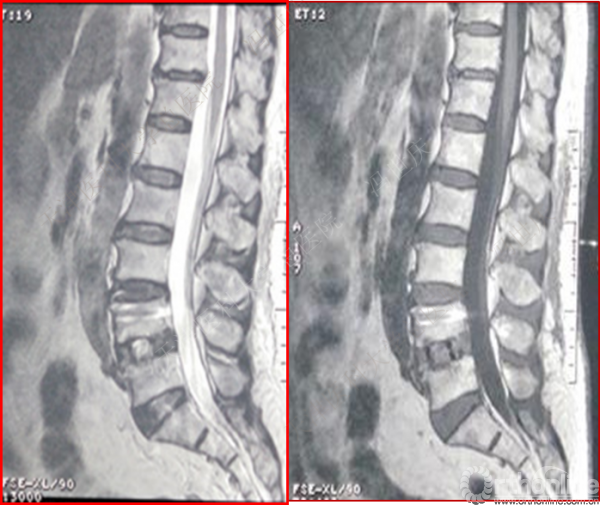

术前

术后